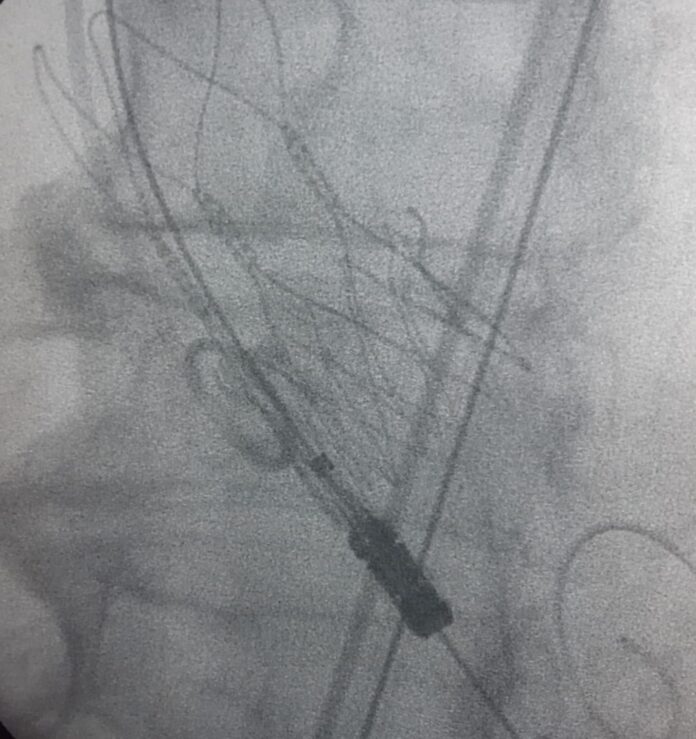

Se trata de un reemplazo Percutáneo de Válvula Aórtica a través de un Tavi, un Implante Valvular Aórtico Transcateter, de manera exitosa en un paciente de 81 años con Estenosis Valvular Aórtica Crítica.

Es un gran avance en esta especialidad, ya que la cirugía se realizó sin la necesidad de abrir el pecho y el corazón, con mejoría inmediata de los Síntomas.